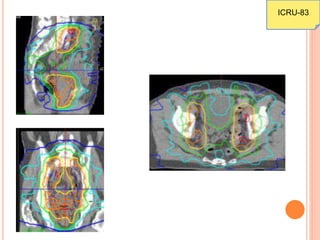

DIFFERENCE BETWEEN

CONVENTIONAL & 3-DCRT

TREATMENT

ICRU-83

IMRT PLANNING OF SAME CASE

PARADIGM SHIFT

 In 3D conformal therapy, ICRU-50 recommended

 Uniform dose to PTV (-5% to +7%)

 Report dose @ isocenter

 IMRT represents ≈40% of the radiation treatment

with a paradigm shift

 Non uniform dose (dose painting)

 Large dosimetric variations

 Isocenter dose is meaningless

 Radiobiological consequence of large

heterogeneous dose is uncertain (ie 180cGy/day

versus 250cGy/day)